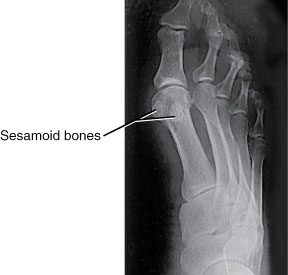

Sezamoidni kosti palca sta del vezivno-ovojničnega kompleksa. V normalnem stopalu sta sezamoidni koščici na stopalu dve koščici v obliki graha, ki se nahajata pod velikimi sklepom palca. Kljub majhnosti sta zelo pomembni pri prenašanju teže in mehaniki stopala. Pri običajnih obremenitvah na njiju delujejo sile, povzročene z do 50 % telesne mase, pri sunkovitih odrivih pa lahko celo večje od 300 %. Velik del telesne teže nosi medialna sezamoidna kost, ki je zato bolj izpostavljena poškodbam.

S pomočjo kliničnega pregleda, rentgenskega slikanja, računalniške tomografije, magnetne resonance ter scintigrafije pridemo do pravilne diagnoze.